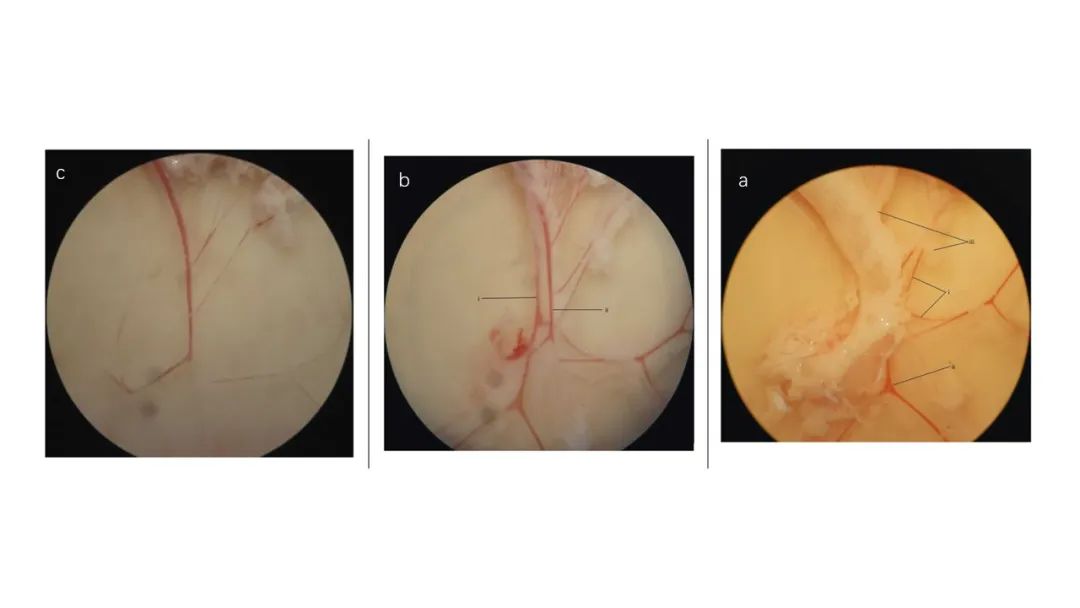

腸系膜血管解剖顯微鏡下圖像。(a)去除結(jié)締組織和神經(jīng)束前,可見(i)動脈、(ii)靜脈和(iii)粘附脂肪。(b)切除大部分結(jié)締組織和神經(jīng)束后。(i)位于(ii)靜脈下方的動脈比后者顯得“更白”。(c)清潔的動脈。